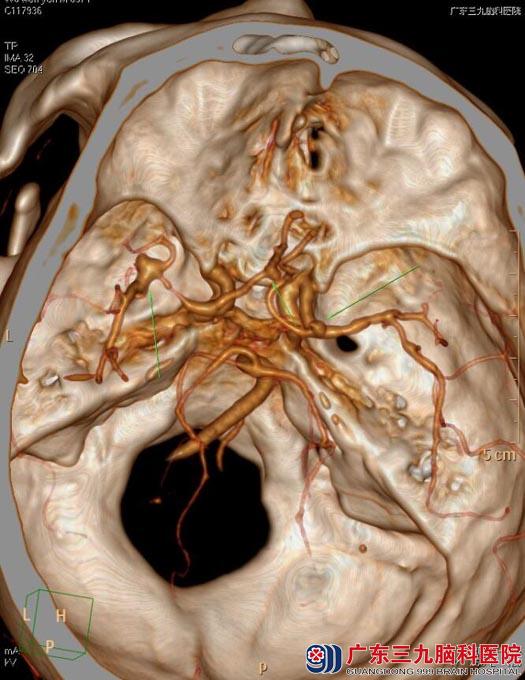

头颅CTA检查显示颅内多发动脉瘤(左侧大脑中动脉M1段分叉处囊状动脉瘤(中型),右侧大脑中动脉M1段起始部、前交通动脉多发小动脉瘤)。进一步行全脑血管造影示:1、右侧大脑中动脉M1起始部动脉瘤,囊状,宽颈,大小约4.5mm×5.0mm,瘤体朝上生长,顶端可见一子囊,大小约1.5mm×2.0mm;2、前交通动脉瘤,囊状,大小约2.5mm×2.5mm,宽颈,朝右侧生长;左侧大脑中动脉分叉处动脉瘤,呈不规则囊状,宽颈,大小约5.5mm*6mm,朝外侧生长。

▲术前CTA